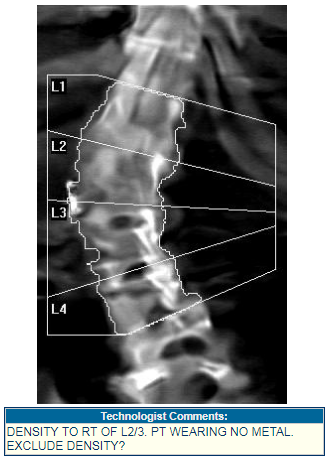

• BoneStation allows technologists to pass information to reading physicians via “scan comments”, which are entered on the DXA and appear in BoneStation.

bsblogrev2